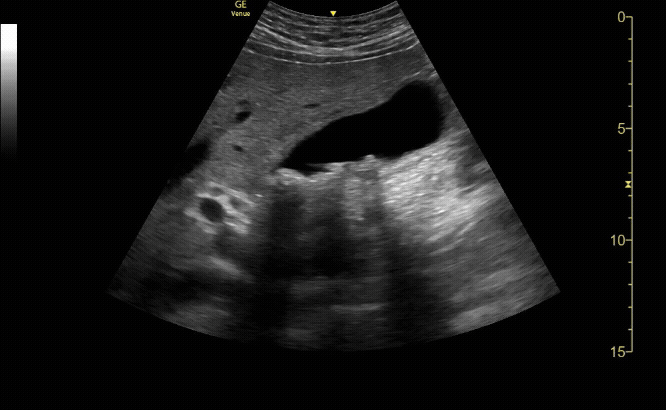

Gallbladder in long view

c/o Alex Alanis, MD

When the gallbladder is in the long axis (the top of the exclamation point), the portal vein is in the short axis (the point of the exclamation point).

The gallbladder may be confused with other fluid filled structures including the portal vein, the inferior vena cava, hepatic or renal cysts, or loculated collections of fluid. These can be more accurately identified with careful scanning in multiple planes and the use of color flow Doppler.